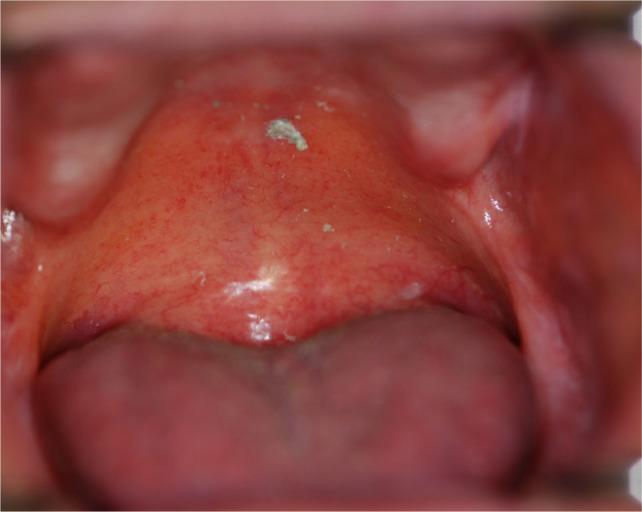

Acute GVHD may manifest in the oral mucosa; however, it often develops immediately following HSCT when routine dental treatment is postponed. Chronic GVHD may manifest in the oral mucosa, the salivary glands and the musculoskeletal compartment. It may indirectly affect the teeth and the oral flora, putting the patient at risk for infections. Importantly, GVHD poses an increased risk for oral cancer.

急性 GVHD 可能在口腔黏膜中表现出来;然而,它通常在 HSCT 后立即发生,此时常规的牙科治疗被推迟。慢性 GVHD 可能在口腔黏膜、唾液腺和肌肉骨骼部位表现出来。它可能会间接影响牙齿和口腔菌群,使患者面临感染的风险。重要的是,GVHD 增加了口腔癌的风险。